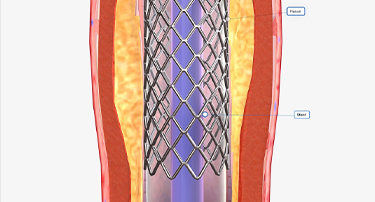

Carotid Artery Stenting vs Endarterectomy: Which Is Better for You

Stroke is a serious condition that happens when a blood clot or broken vessel prevents blood from reaching the brain. Due to this, one can experience paralysis, muscle weakness, slurred speech, and memory challenges, or even seizures.

Carotid Stenting: A Life-Saving Procedure to Prevent Stroke

You might face many instances in life where planning ahead could make all the difference. For example, if you want to crack a competitive exam, you analyze the past papers, concentrate most on the important topics, and then study hard to get the best outcome.